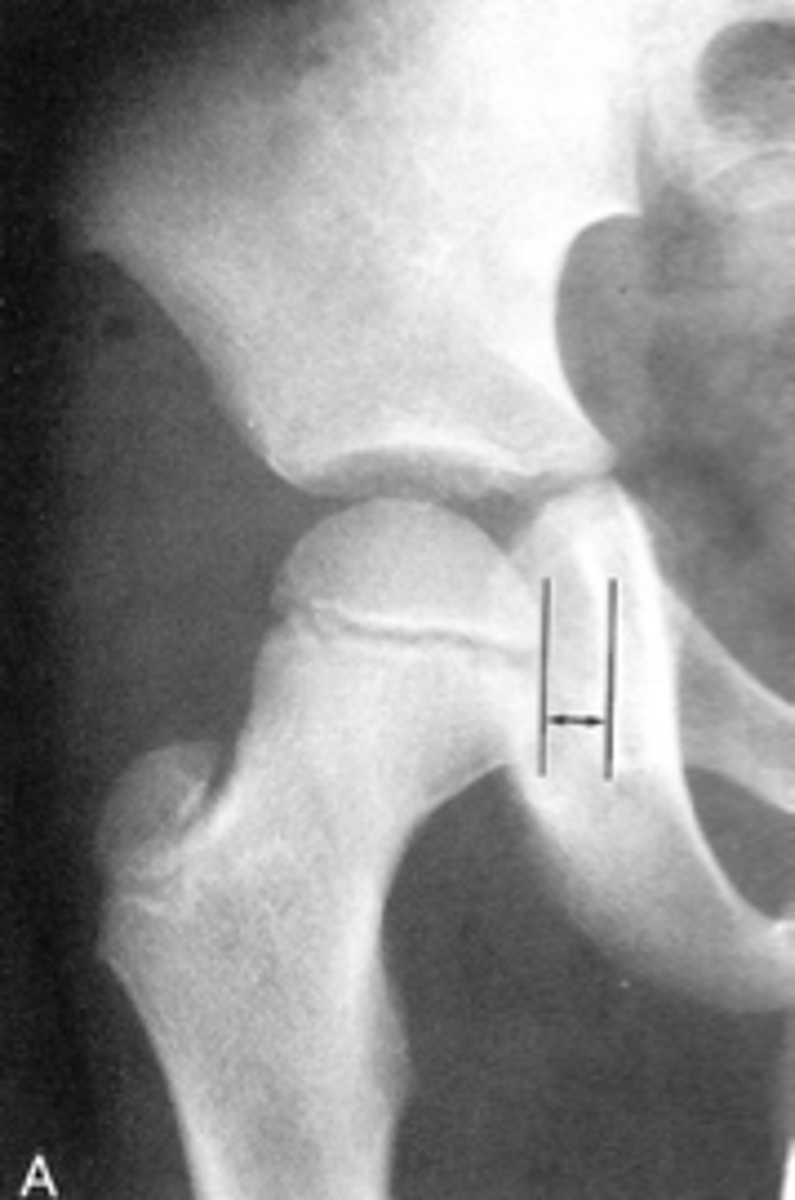

Normal vascular channel

ID

<p>ID</p>